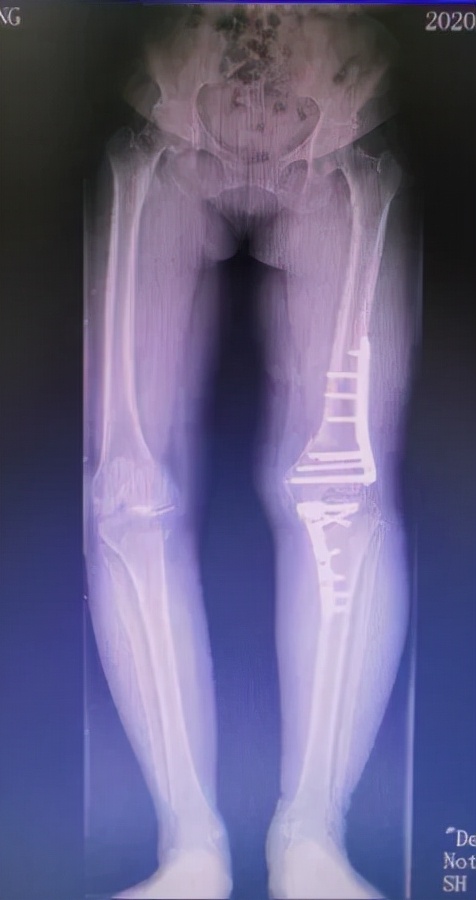

术后1年

通过术前在计算机上精确规划截骨线及矫正角度后,刘万军主任团队对赵女士的左膝同时进行了股骨远端截骨术+胫骨高位截骨术。先取左膝关节的正中切口,行内松解后,按标准手术行髌骨修整。股骨切骨完整后,试装假体复位,调试后用骨水密固定安装假体。之后取左膝关节屈膝90度,采用外侧倒T行切口,分离胫骨外侧组织,在胫骨平台远侧2cm处截骨,用C形臂X线机检查位置,反复检查下肢对线,在腓骨前方行内固定。手术进行的非常顺利,出血少,历时约3小时10分钟。术后赵女士的膝关节疼痛消失,膝内翻畸形得到明显改善。

刘万军主任介绍到,为了避免截骨术后关节线倾斜的发生,越来越多的学者主张在复杂畸形中应行股骨和胫骨的双部位截骨。股骨和胫骨双部位截骨的优势在于可以在维持关节线位置的同时,恢复膝关节正常解剖角度,从而保证下肢应力的合理分布。然而其也存在一些缺点,比如造成的创伤较大、术中发生并发症的可能性增加、康复及骨愈合的时间延长等。